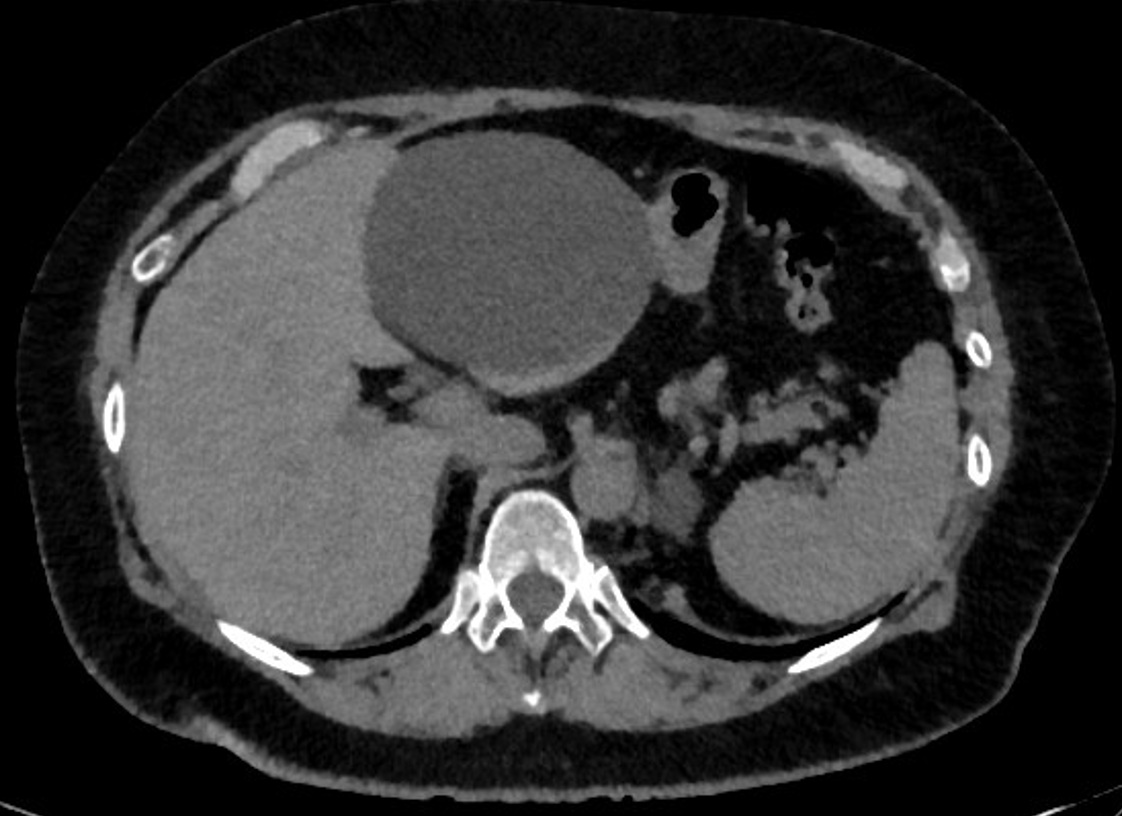

Дебютом своего заболевания считает июнь 2018 г, когда после употребления соленой рыбы почувствовала боль в правом подреберье, тошноту, появившуюся многократную рвоту. Из анамнеза известно о наличие у пациентки желчнокаменной болезни, хронического калькулезного холецистита. Данное состояние связывала с обострением имеющегося заболевания. После купирования болевого синдрома обратилась в поликлинику по месту жительства, где было выполнено УЗИ органов брюшной полости, при котором впервые было обнаружено анэхогенное включение размерами 10,0*8,7*7,6 мм с ровными контурами. Была заподозрена киста левой доли печени или головки поджелудочной железы. Для уточнения локализации образования было рекомендовано выполнение спиральной компьютерной томографии органов брюшной полости. При этом было выявлено крупное жидкостное образование в проекции III сегмента, с переходом на II сегмент, размерами 89х79х88мм (рис. 1.).

Рис. 1. Киста печени.

Fig. 1. Liver cyst.